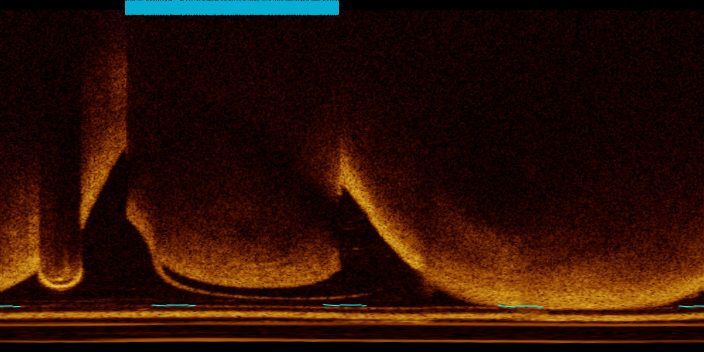

Intracoronary optical coherence tomography (OCT) is an invasive imaging modality that yields consecutive high-resolution cross-sectional images of a coronary artery segment. OCT can offer accurate information on the vessel microstructure, such as plaque presence and characteristics, as well as details regarding the state of stented lesions[1]. This imaging technique has been proven to provide valuable complementary information to X-ray angiography in guiding percutaneous revascularization [2, 3]. During intracoronary OCT acquisition, the OCT probe emits near-infrared light in a helical pattern, acquiring multiple attenuation lines (A-lines) and forming a 3D volume, which is referred to as a pullback. An OCT pullback consists of a few hundred cross-sectional images of the coronary artery in Cartesian coordinates, referred to as frames. Each frame typically has an in-plane resolution of 10-15 µm, and the length of the pullback can reach 150 mm. During OCT imaging, blood must be completely flushed from within the lumen. Incomplete flushing can leave blood residues in the lumen and cause the formation of gas bubbles within the catheter. Blood residues and gas bubbles cause attenuation artifacts, casting shadows that prevent the light from reaching the arterial wall (Figure 1). The presence of these artifacts may mask critical features, leading to incorrect assessment of an intracoronary OCT exam and resulting in misdiagnosis or suboptimal decision making. Automated detection and severity assessment of these artifacts could provide important feedback to the operator; the detection of severe attenuation artifacts can suggest re-acquisition of the pullback, whereas detection of mild artifacts can provide useful information during image interpretation and help identify areas where minor corrections can enhance the overall image quality.

To define the reference standard, A-lines were annotated using the brush tool within ITK-SNAP[11] to paint the corresponding label over the artifact-affected arcs. This operation was performed on images visualized in Cartesian coordinates. Figure 1 shows an example of the annotated arcs. The annotation of each frame was then processed to derive a vector , where is the number of A-lines per frame. The pullbacks and frames selected for annotation were chosen such that the annotated dataset would be heterogeneous in terms of artifact appearance. Possible variations in appearance included high versus low mixing of blood residues within the lumen and the size of the gas bubbles. The dataset also included frames featuring red thrombi, pathological structures that visually resemble blood artifacts.